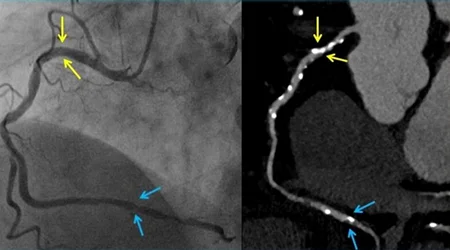

- تست ورزش قادر به تعیین نوع رگ مبتلا ، تعداد رگ های مبتلا و محل انسداد رگ قلب نیست. برای تعیین این موارد بعد از مثبت شدن تست ورزش ، باید آنژیوگرافی عروق کرونر انجام شود.